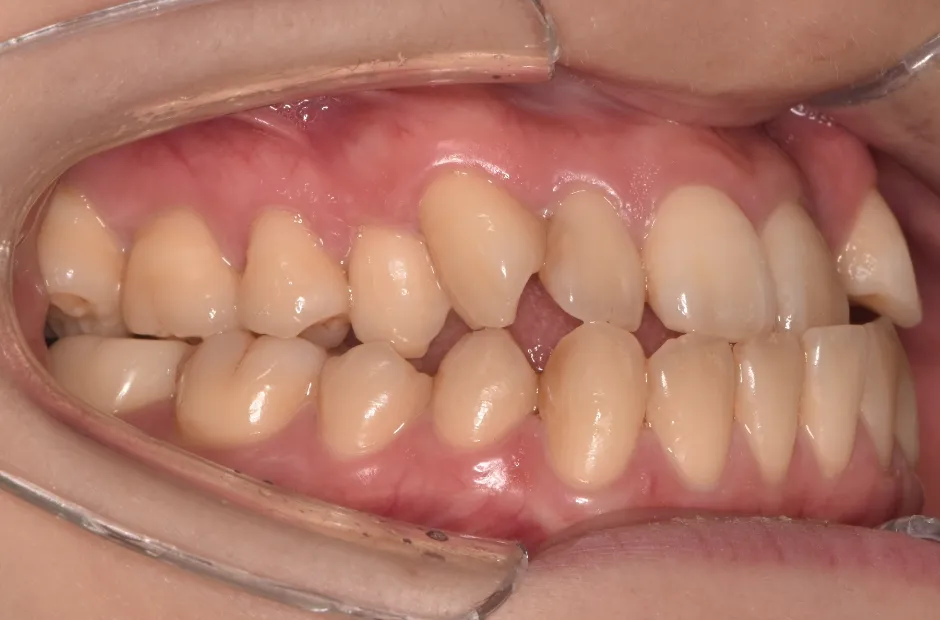

反対咬合

| 診断名・主訴 | 下顎前突、叢生 |

|---|---|

| 年齢・性別 | 23歳・女性 |

| 治療期間・回数 | 3年 |

| 治療に用いた主な装置 | 上顎5,5 下顎4,4 |

| 抜歯部位 | 舌側矯正 |

| 治療費 | 100万円(税抜) |

| リスク・副作用 | 装置による違和感・疼痛・歯肉退縮・歯根吸収・虫歯のリスクなど |

治療前

治療中